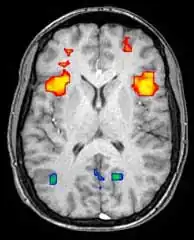

Функциональная магнитно-резонансная томография

Функциональная магнитно-резонансная томография (фМРТ) основана на парамагнитных свойствах оксигенированого и дезоксигенированого гемоглобина и дает возможность увидеть изменения кровообращения головного мозга в зависимости от его активности. Такие изображения показывают, какие участки мозга активированы (и каким образом) при исполнении определённых заданий.

Большинство фМРТ-томографов дают возможность представлять исследуемому разные визуальные изображения, звуковые и тактильные стимулы и производить действия типа нажатия кнопки или движения джойстиком. Следовательно, фМРТ можно использовать, чтобы показывать структуры мозга и процессы, связанные с восприятием, мышлением и движениями. Разрешение фМРТ на данный момент 2—3 мм, ограниченное кровоснабжением, влияющим на нейрональную активность. Она существенно заменяет ПЭТ при исследовании типов активации головного мозга. ПЭТ, однако, одерживает значительное преимущество, будучи в состоянии идентифицировать специфические клеточные рецепторы или (моноаминовые трансмиттеры) связанные с нейромедиаторами, благодаря визуализации меченных радиоактивно рецепторных «лигандов» (рецепторный лиганд — химическое вещество, связанное с рецептором).

фМРТ используют как для медицинских исследований, так и (всё шире) в диагностических целях. Так как фМРТ исключительно чувствительна к изменениям кровообращения, она очень хорошо диагностирует ишемию, как например при инсульте. Ранняя диагностика инсультов всё важнее в неврологии, так как медикаменты, растворяющие свернувшиеся сгустки крови, можно использовать в первые несколько часов и при определённом типе инсульта, в то время как они могут быть опасными при дальнейшем использовании. фМРТ в таких случаях дает возможность принять правильное решение.

фМРТ можно использовать также для распознавания мыслей. В эксперименте с точностью 72 %—90 %[5] фМРТ смогла установить, какой набор картинок смотрит испытуемый[6]. Скоро, по мнению авторов исследований, благодаря этой технологии можно будет установить, что именно видит перед собой испытуемый[6]. Эту технологию можно будет использовать для визуализации снов, раннего предупреждения болезней головного мозга, создания интерфейсов для парализованных людей для общения с окружающим миром, маркетинговые рекламные программы и борьба с терроризмом и преступностью[6].